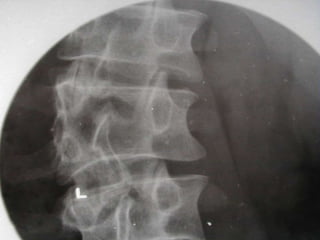

Lordosis Lumbar

● Sobre la proyección lumbar lateral se

trazan lineas paralelas a lo largo del

platillo terminal superior de L1 y de la

base del sacro.

● Se trazan las perpendiculares de esas

lineas y se mide el angulo resultante.

● Normal es de 50-60 grados.